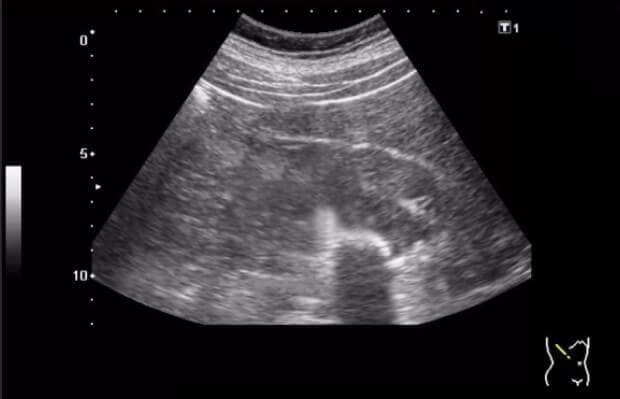

Za mjesec dana ultrazvuk je pokazao da se cista duplo smanjila - sa 20 mm je spala na 10 mm! A dva od tri kamena su se istopila i izašla (sjećam se da me boljelo prilikom mokrenja par dana prije ovoga). Onda sam prešla na običnu dozu. Za mjesec dana, doktor je bio u šoku kad je uradio ultrazvuk - bubrezi su bili čisti!